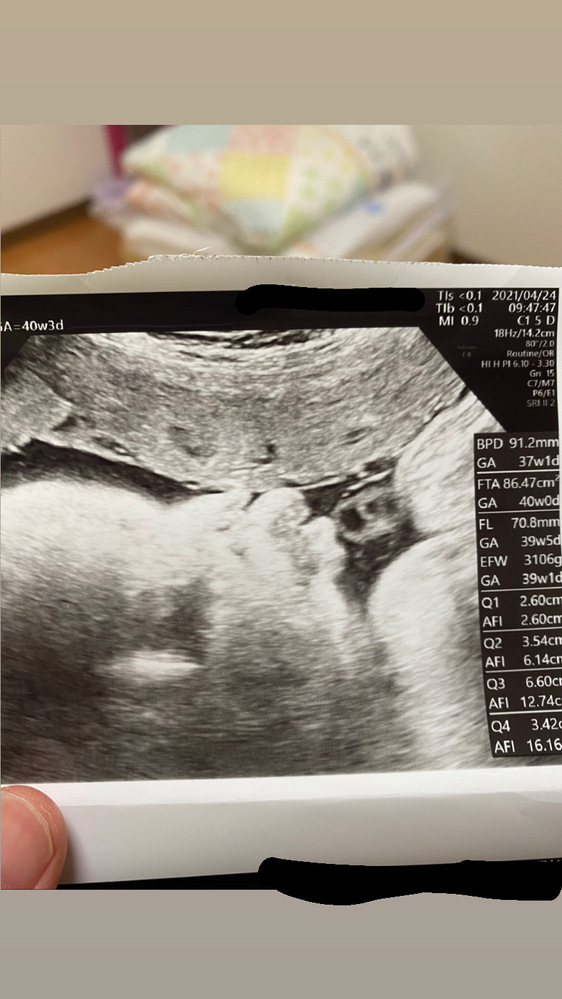

4D超音波エコー横顔も。 妊娠39週4日、予定日まであと3日です。 健診の結果、子宮口が約15cm開いているとのことでした! ! 前回の初産のときは、お腹が定期的に痛くて「陣痛きた」と思って病院行ってみてもらった時点が1~2cmの開きで、その日の夜23時 エコーによるダウン症の判断 最近では、 エコーを使うことによって、ダウン症の判断ができるか どうかが話題になることが多いです。 エコーというのは、超音波を用いて胎児の様子を観察することであり、顔や手、足などの形がはっきりと分かります。 このエコーを用いて 胎児の横顔を女の子は妊娠7ヶ月で判明が多い妊娠24週~26週のエコー写真 妊娠8ヶ月で可能性が確実に!?妊娠28週・30週のエコー写真 妊娠9ヶ月まで隠していた男の子も妊娠33週・34週のエコー写真 妊娠15週目のエコーで性別が分かったというケースも!

30週 エコー 横顔-妊娠30週2日(30w2d)の超音波(エコー)写真 妊娠30週2日(30w2d)の超音波(エコー)写真 妊娠30w2d 名前あい 年齢29 妊娠週30w2d 2週間で300g増えて1517gで標準だねと言われました。 逆子も直ってて2人目なので回ったのがすぐ分かりました。 ダウン症のエコー特徴 写真でみる手足・頭・BPD・NT・FL徹底解説 voicyでインターネットラジオを配信しています! 棚を整理していると、アップ君のエコー写真が出てきました。 懐かしさに浸りながら、ふと疑問に思ったことがあります。 出生前診断をし

30週検診と初めての横顔 妊娠30週になりました。 ちょっと焦ってきた。 み、見えない 慌ててカップを当てる。 体重の増加もそれほどでもなくホッ。 妊娠前より6キロ増。 今回はエコーバッチリ見えました。 顔を隠すことが多くて見られなかった。4Dエコーでは全身が映り、性別がわかることもあります。ここでは、妊娠週の母子の様子やエコー検査でわかる異常について解説する他、胎動やお腹の大きさ、性別に 4Dエコー体験!8ヶ月30週の赤ちゃんはこんな感じ25週3日の4dエコーと2dエコー どちらの写真も横顔の写真ですが、これを見たとき 上唇出過ぎじゃない?鼻より出てる!まさかこんなはずはない!と思いました。 しかし産まれたばかり我が子を見ると 上唇めっちゃ出てる!

チャーミー小結さんの妊娠30週目のエコー写真 命の始まりは神秘的! 2D・3D・4Dのエコー写真で見る「私と赤ちゃんの実録260日」 口をキュッとつぐむ様子も愛おしい表情。 この頃は便秘がひどく、「酸化マグネシウム」を医師に処方してもらいました 25週3日の4dエコーと2dエコー どちらの写真も横顔の写真ですが、これを見たとき 上唇出過ぎじゃない?鼻より出てる!まさかこんなはずはない! と思いました。 しかし産まれたばかり我が子を見ると 上唇めっちゃ出てる!!笑 エコーすごい!! 27週3日おなまえ ハルママ ねんれい 30歳 妊娠

知っておくと楽しみ倍増 エコー写真 の見方と用語 17年4月19日 ウーマンエキサイト 2 2

現在40週の赤ちゃんのエコー写真です 横顔なのですが唇が3つぐらいに割れ Yahoo 知恵袋

妊娠30週です 赤ちゃんのエコー写真を見て 口唇裂じゃないかとふと不安 Yahoo 知恵袋

妊娠30週目 30w0d 6d のエコー写真とエピソード 妊娠8ヶ月 Cozre コズレ 子育てマガジン

妊娠30週4日 30w4d の超音波 エコー 写真

妊娠30週3日 30w3d の超音波 エコー 写真

妊娠30週 胎児の体重や成長と妊婦のお腹の大きさ 症状 エコー写真付き ままのて

妊娠30週1日 30w1d の超音波 エコー 写真